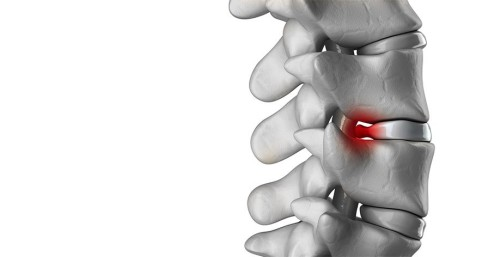

Фото: Травмована область хребта

У сучасній медицині компресійний перелом хребців визначається як порушеної цілісності елементів хребта, що відповідає за опорно-рухові функції людського тіла. У подібних випадках спостерігається значне стиснення і зменшення висоти пошкоджених хребців.

Виникнення травми в області хребта пояснюється різким згинанням або форсованої навантаженням, що є спрямованою уздовж його осі. Нерідкими виявляються випадки, коли подібні згинання поєднуються з інтенсивно спрямованим ударом в дану область тіла людини.